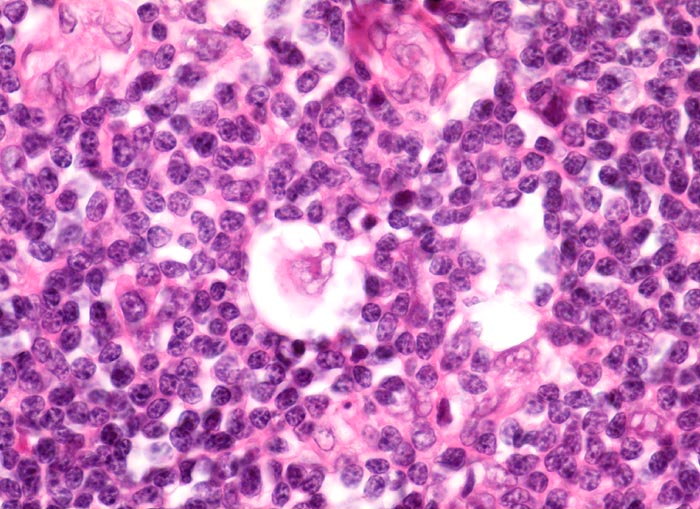

Morphologische Merkmale:

• Zerstörung der Lymphknotenarchitektur.

• Von breiten Bindegewebssträngen abgegrenzte Knoten.

• Die Knoten bestehen vorwiegend aus einem Mischzellinfiltrat reaktiver Zellen: Lymphozyten, Histiozyten, eosinophile Granulozyten und Plasmazellen.

• Reed-Sternbergzelle mit spiegelbildlich angeordneten Kernen mit sehr grossen eosinophilen Nukleolen.

• Einkernige Hodgkinzelle mit prominentem Nukleolus umgeben von einem Retraktionsartefakt (Lakunarzelle).